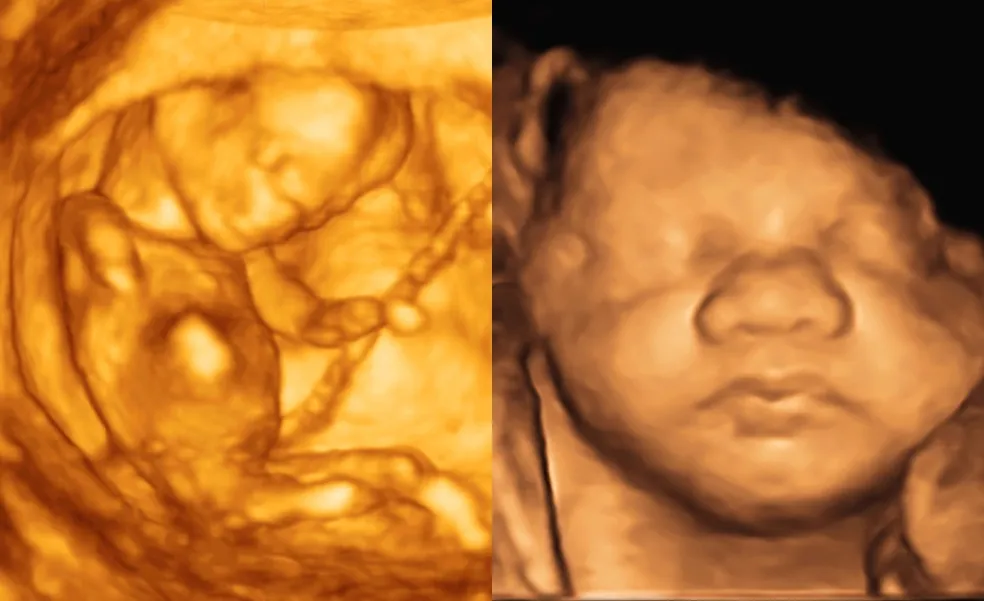

Chystáte sa na 3D/4D ultrazvuk? Toto všetko je dobré vedieť vopred!

3D ultrazvuk 4D ultrazvuk

Tehotenstvo je obdobím plným očakávania, radosti a miliónov otázok. Jednou z vecí, na ktorú sa budúci rodičia často najviac tešia, je možnosť vidieť svoje bábätko ešte predtým, než príde na svet. Kým klasický ultrazvuk ukáže základné obrysy a pohyby, 3D a 4D ultrazvuk prinášajú oveľa viac – reálny pohľad na malé tváričky, grimasy, úsmevy či na to, ako si bábätko cmúľa palec.

3D ultrazvuk už dokáže vytvoriť trojrozmerný statický obraz bábätka. Umožňuje pozorovať tváričku, končatiny, mimiku či pohyb rúk v omnoho reálnejšej podobe než 2D snímky. Tento typ ultrazvuku si rodičia často vyberajú kvôli emocionálnemu zážitku a pamiatke.

4D ultrazvuk je vlastne „živá verzia“ 3D – zachytáva pohyby bábätka v reálnom čase. Vidieť, ako si cmúľa palec, zíva alebo sa usmieva, je nezabudnuteľné. Aj keď nejde o povinné vyšetrenie, 4D ultrazvuk ponúka budúcim rodičom výnimočné spojenie s ich dieťatkom ešte pred pôrodom.

Najväčším lákadlom 3D a 4D ultrazvuku je pohľad na bábätko tak, ako ho len málokto zažije ešte pred narodením. Rodičia môžu vidieť detailne tvar tváričky, nosík, pery, viečka aj mimiku. Bábätko často otvára a zatvára oči, zíva, usmieva sa alebo si cmúľa palec – a v 4D verzii to všetko vidno v reálnom čase, ako na videu.